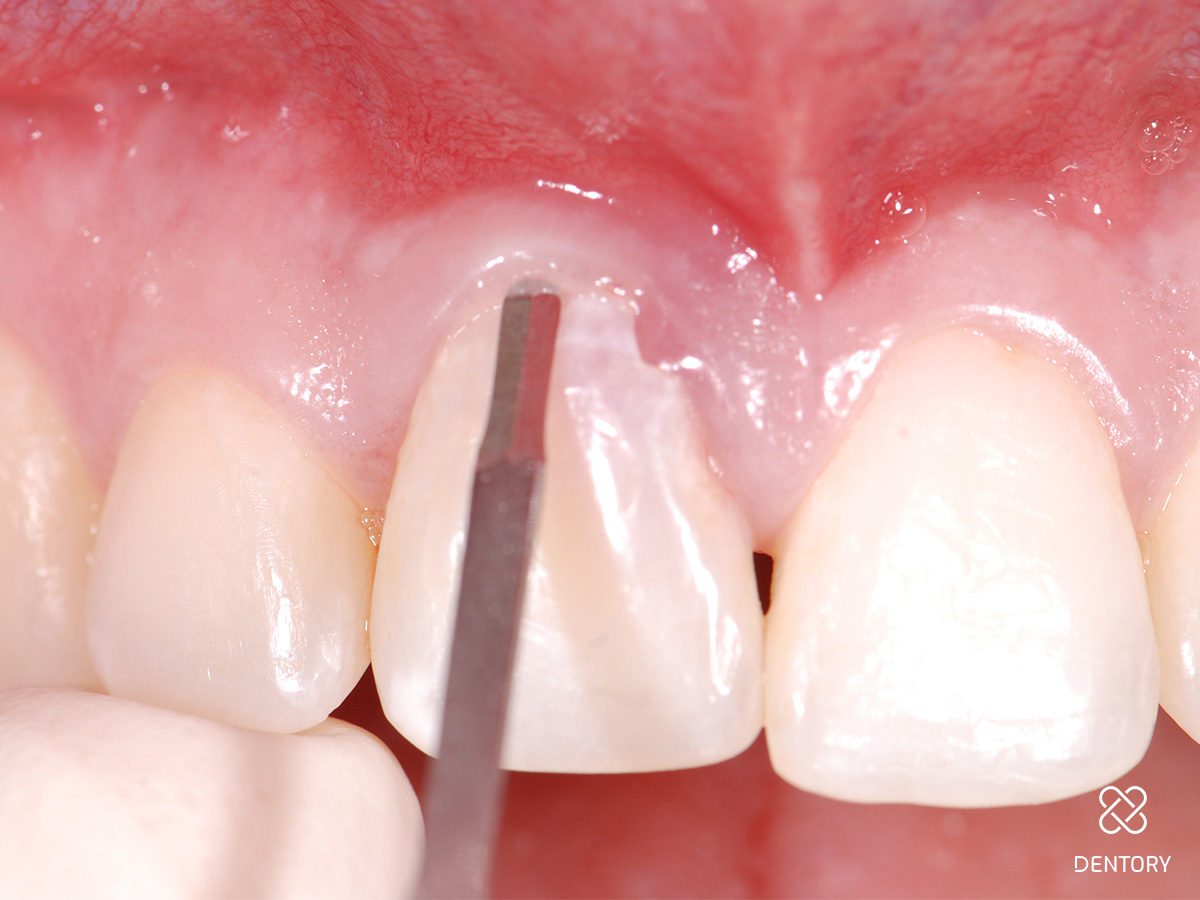

Abbildung 2

Schonende Zahnentfernung: Behutsames Durchtrennen der paradontalen Fasern mittels Mikroskalpell...